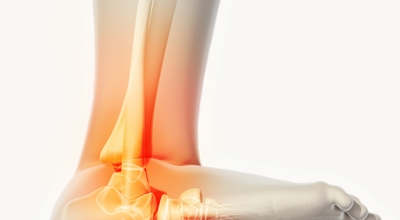

족저 근막이란 발가락 시작지점부터 발뒤꿈치뼈까지 발바닥 전체를 감싸고 있는 두꺼운 막을 말해요. 족저 근막은 발바닥 아치를 지속시켜 발바닥이 지면을 내딛음으로써 나타나는 충격을 흡수하는 중요한 역할을 수행하고 있어요. 이 족저 근막에 일차적으로 서서히 조직 손상이 일어나고 계속적인 활동으로 인해 염증이 커지면서 발 뒤꿈치 부근 통증을 유발하게 되는데 염증은 무리하고 반복적인 동작, 과도한 사용으로 마찰에 의해 발생해요.